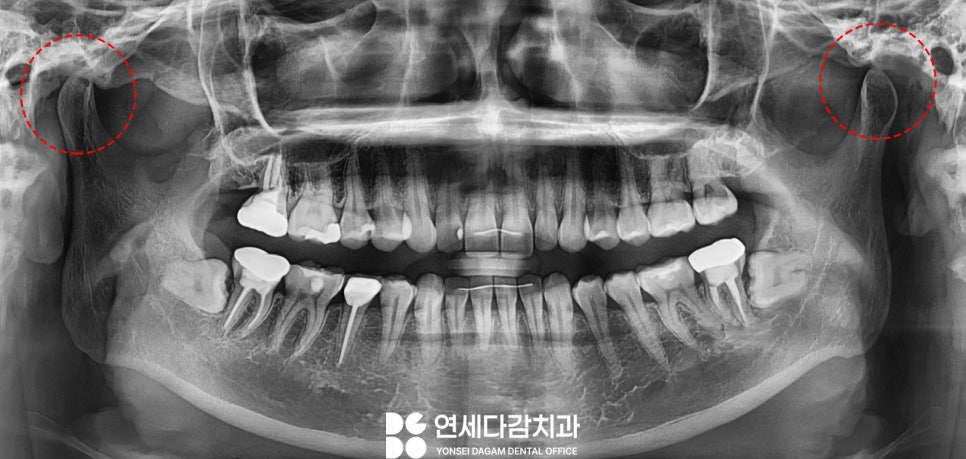

입이 잘 안 벌어지고 통증을

호소할 땐 정확한 검진을 위해

엑스레이 사진을 촬영해야 됩니다.

우선 일반 파노라마를

촬영하여 교근을 잘 살펴봅니다.

이때 턱 근육이 비대해져

양측 교근과 측두근이 과도하게

발달된 것을 알 수 있었습니다.